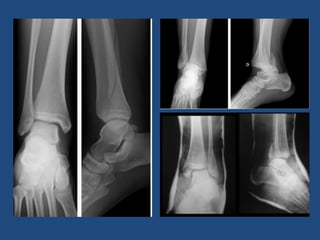

Radiología

• Lateral

• AP

• Axial

• TAC